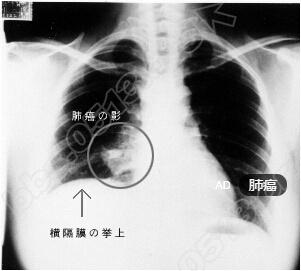

前不久发布的癌症数据最新播报显示,肺癌依然是高局男性癌症疾病发病率的首位,是女性癌症发病率的第二位。专家预测,我国肺癌的发病率还处在快速的上升阶段,且来势汹汹。那么面对穷追不舍的肺癌,我们如何进行早期发现、早期治疗成了战胜肺癌的关键所在。$ Z% w  r  ^0 U8 }& y

在当今先进的诊断设备和医疗技术条件下,早期发现肺癌并进行彻底根治并不困难,困难的是人们普遍缺乏主动查体的意识,以至于,大多数肺癌患者一发现就已经是晚期,失去了治疗的最佳时机。. n% b$ O$ v" c' j$ G: w& w( {% |

南通市第六人民医院胸外科主任范岗说:“早期肺癌没有任何症状,在临床上因出现症状第一次就诊时85%的肺癌患者就已经是晚期了,晚期肺癌的总治愈率只有不到5%,而最早期的一期A的患者手术后5年的生存率可达70%-90%。国外的经验显示,通过低剂量CT(LDCT)实现的肺癌早诊能降低总死亡率20%,这是近年来对提高肺癌治愈率的最大贡献。”$ o2 C# m5 {' q) g

早期肺癌主要表现为无症状的肺部小结节,现在各单位每年都会组织职工进行常规体检,其中有一项是拍胸片,有些人认为胸片正常就没事儿了,实际上,要发现早期肺癌还是得依靠CT检查。根据NCCN肺癌早期筛查指南,范岗建议对肺癌的高危人群应该每年进行一次低剂量CT检查,如55岁以上、吸烟30包年(每天吸烟包数乘以年数)和50岁以上吸烟20包年且有危险因素者。